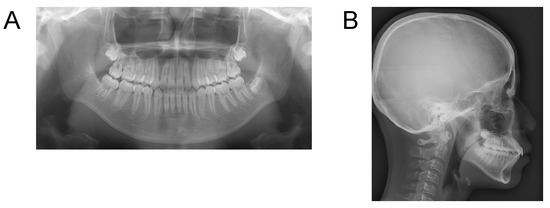

Case 2. Findings from initial examination